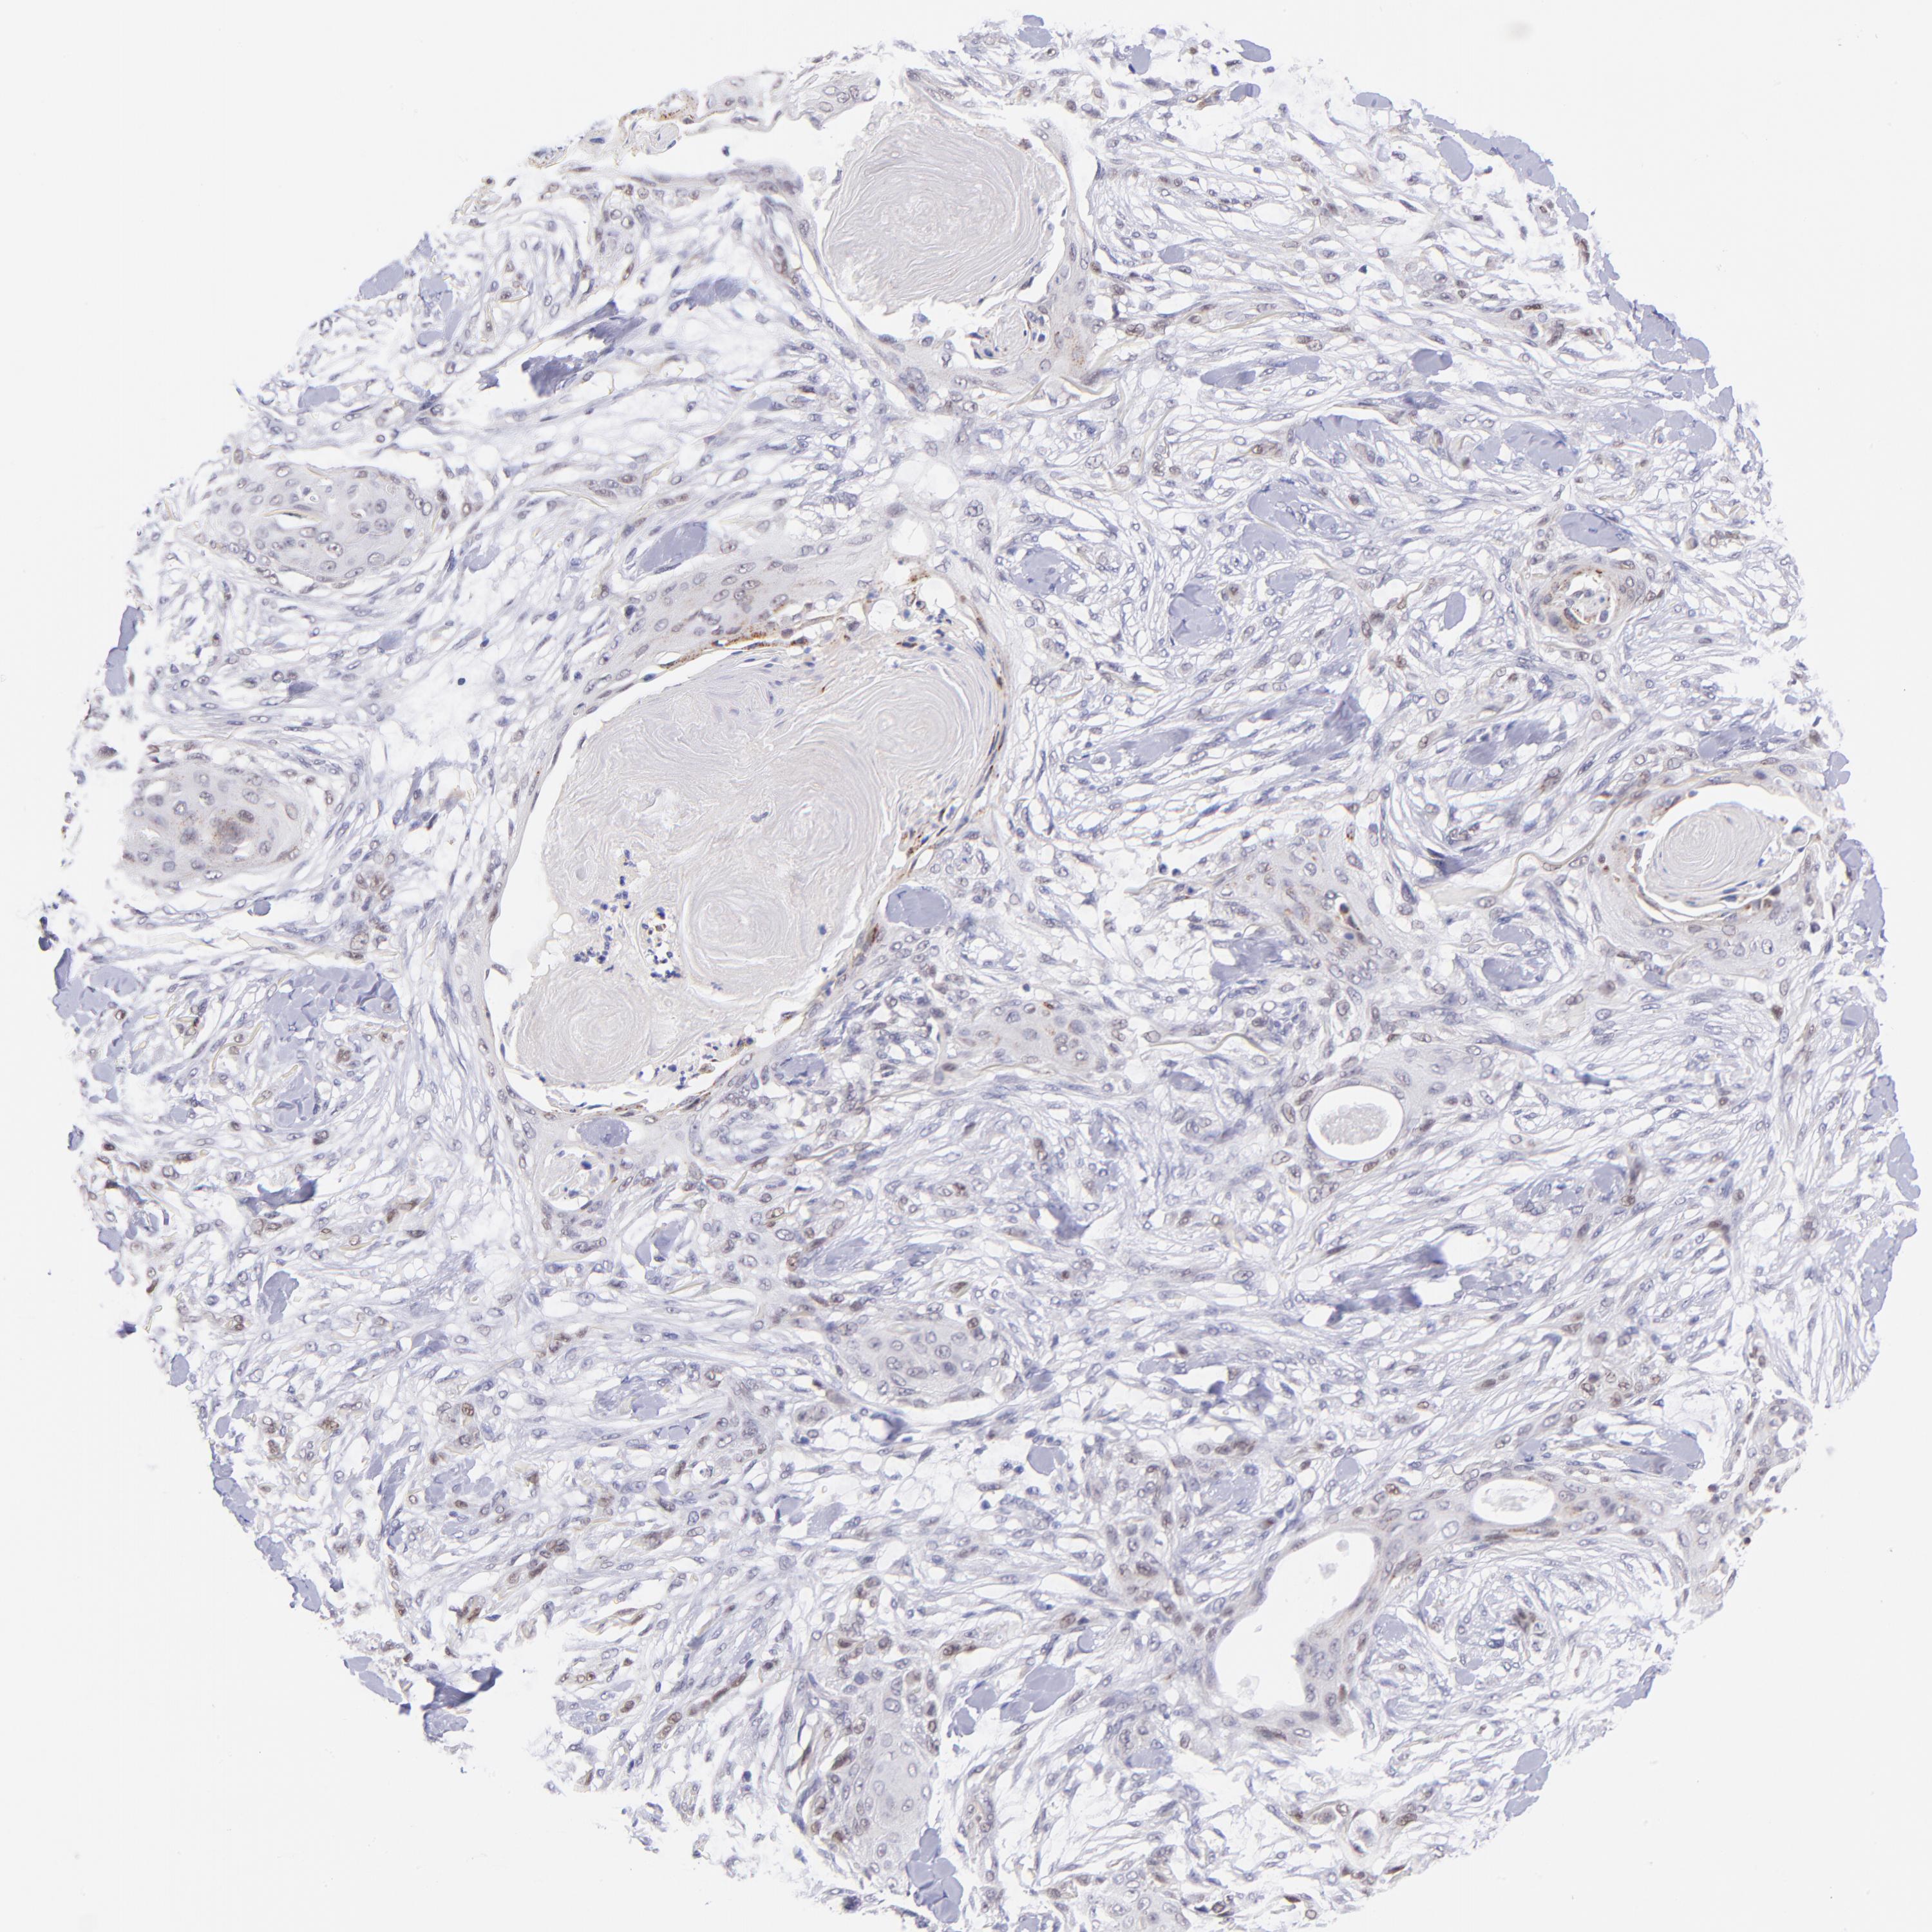

SKIN CANCER - Protein expressioni

A mouse-over function shows sample information and annotation data. Click on an image to view it in a full screen mode. Samples can be filtered based on level of antibody staining by selecting one or several of the following categories: high, medium, low and not detected. The assay and annotation is described here.

Antibody stainingi

Antibody staining in the annotated cell types in the current human tissue is reported as not detected, low, medium, or high, based on conventional immunohistochemistry profiling in selected tissues. This score is based on the combination of the staining intensity and fraction of stained cells.

Each image is clickable and will lead to virtual microscopy that enables deeper exploration of all samples and also displays staining intensity scores, fraction scores and subcellular localization as well as patient and tissue information for each sample.

Antibody HPA001923

Squamous cell carcinoma, NOS

Basal cell carcinoma